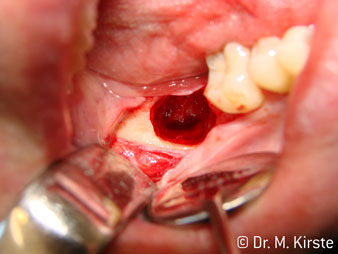

45° açılı angldruva geniş avantaj yelpazesi sebebiyle özellikle seçildi. Bu enstrümanın geliştirilme nedeni olan cerrah meslektaşlarım angldruvaların kısıtlı alanlardaki çalışma yeteneğini yakında takdir edeceklerdir. Özellikle gömük diş çekimlerinde (res. 2) yumuşak dokunun yanak bölgesine doğru yarılmasına gerek kalmaz(res. 3). Angldruvanın kafa dizaynı sayesinde retromolar bölgede hızlı ve güvenli çalışma sağlar.

Hızlı çalışmadan bahsetmişken: angldruva, 100,000 rpm üzerinde çalışırken aynı anda profesyonel bir soğutma sağlanır

Angldruva kafası içindeki profesyonel tasarımlı dişliler frezin sessiz çalışmasını garanti eder; kök separasyonu yapılırken atravmatik operasyona olanak verir. (res. 4-9).